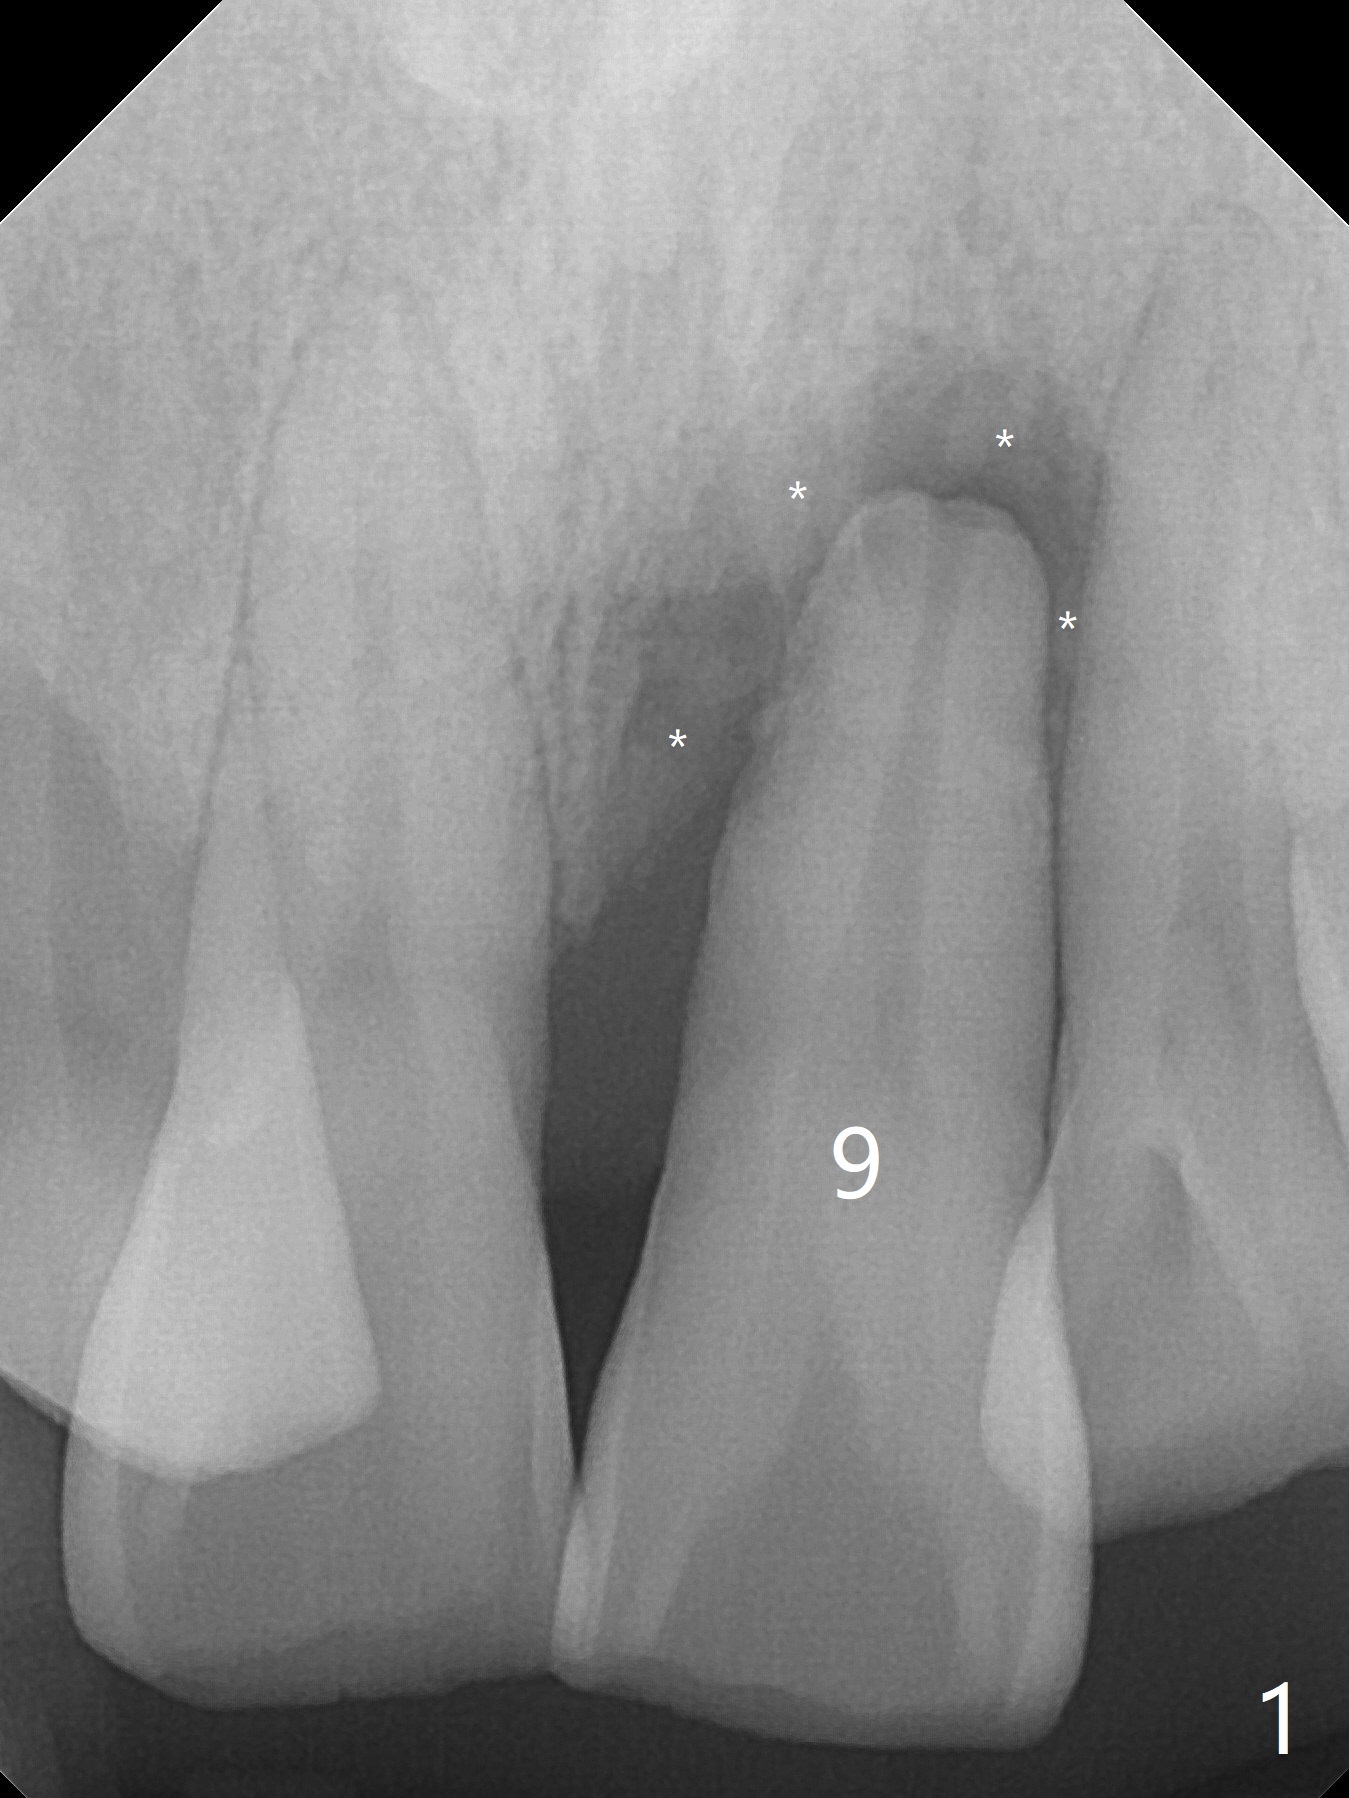

Immediately preop PA confirms loss of the buccal plate at #9 (Fig.1 *). In contrast the palatal crest is ~ 4 mm subgingival (WNL) after extraction. When initial osteotomy reaches 18 mm, there is moderate hemorrhage, probably due to close to the nasal floor (Fig.2 red dashed line). Following sequential osteotomy, a 3.8x15 mm dummy implant is placed partially (Fig.3 (pink: apical osteotomy)). After placement of an implant with the same dimension as the dummy's (Fig.4), PRF is laid against the inner surface of the buccal defect and allograft (Fig.5 *) is packed mainly in the buccal gap before and after insertion of a 4.5x5(4) mm abutment. The patient is satisfied with the immediate provisional (Fig.6: 1 week postop). The buccal margin of the provisional is shortened with exposure of bone graft to facilitate gingival downgrowth (Fig.6: 1 month postop). The buccal plate seems to collapse nearly 2 months postop (Fig.8 *), probably due to loss of the bone graft. The abutment is exposed buccally (Fig.9). The margin of the abutment is reprep and the provisional is relined so that the margin of the provisional is palatal to the buccal gingival margin. In 2-3 weeks, a temporary abutment will be used to bulk the buccal gingiva. The gingiva seems to have downgrown; the buccal plate collapse appears normal nearly 3 months postop (Fig.10). The patient is more concerned about cross bite at #7. A temporary abutment is not used. The bone graft remains in place 3.5 and 4.5 months postop (Fig.11,12 *). Between 3 and 4 months postop, the mesial surface of the abutment has been trimmed (Fig.12 >). Since the mesial surface of the tooth #10 will be reduced (white curved line) to correct the upper dental midline, an angled abutment (red line) seems to be necessary to shift the provisional distal.